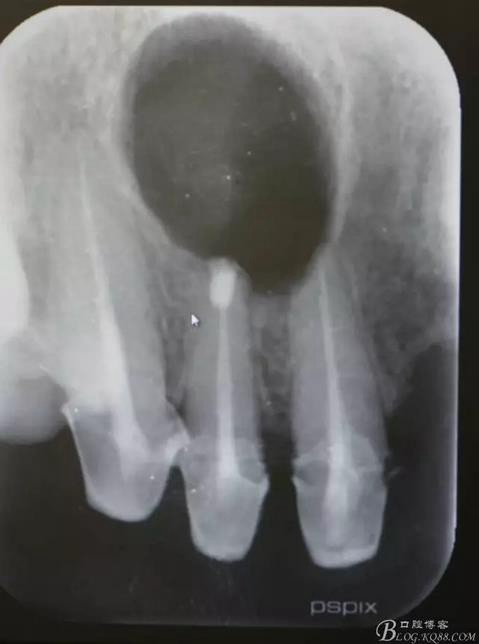

患者、王xx、女、56歲。主訴:右側(cè)上顎部反復(fù)腫痛兩年。??茩z查:上半口烤瓷橋修復(fù),12腭側(cè)隆起,捫診有輕微觸痛。X光:12根尖有圓形規(guī)則陰影,范圍月、約1.0x1.2cm,邊界清晰,11、12根管治療不完善。診斷:12根尖囊腫。治療計劃:1.行11、12根管治療術(shù)。2.擇期行根尖手術(shù)。患者同意治療方案,簽知情同意書。

圖1.術(shù)前的根尖片影像檢查:11、12根管治療不完善